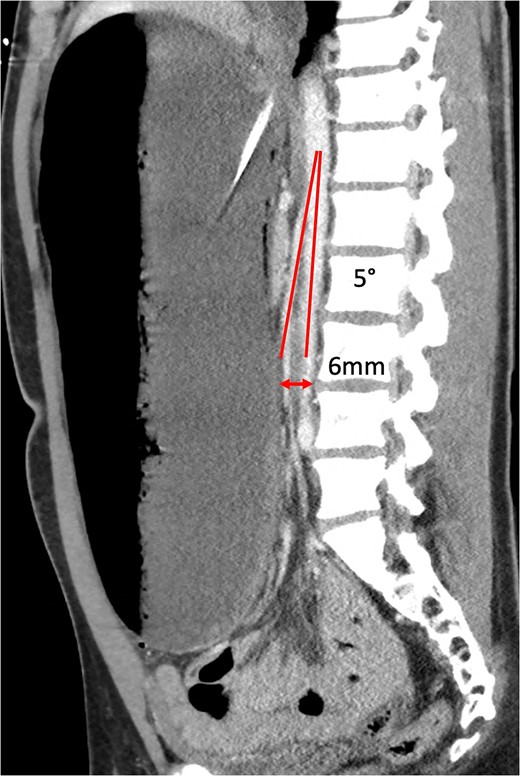

An 18-year-old male presented with severe abdominal pain, distension, and vomiting after a buffet meal. He had a BMI of 22 (weight 71 kg, height 181 cm) and no significant medical history or recent weight loss. He was normotensive (110/80), tachycardic (>120 bpm), and febrile (38.9°C). Examination revealed lethargy, a grossly tympanic, distended and tender abdomen. Biochemical tests showed severe lactic acidosis (pH 7.13, lactate 13.7), leukocytosis (white cell count 21×108) and acute kidney injury (creatinine 203 μmol/L, glomerular filtration rate 40 ml/mn/1.73m2). CT scan revealed acute gastric dilatation (35×19×12 cm), gastric pneumotosis and portal venous gas (Figs 1 and 2) with aortomesenteric angle of 5° and distance of 6 mm (Fig. 3). There were broad differentials considered at the time of presentation including both mechanical and functional aetiologies (Table 1).

Sagittal CT showing aortomesenteric angle (5°) and aortomesenteric distance (6 mm).

The normal aorto-mesenteric angle is between 38° and 65° [14] and distance is 10–28 mm [15], whereby fibrofatty tissue bolsters the space between SMA and AA. An angle ≤22° and distance ≤8 mm is highly sensitive and specific as a radiological diagnostic criteria for SMA syndrome [16]. Our patient’s respective measurements of 5° and 6 mm fall far below the defined thresholds.